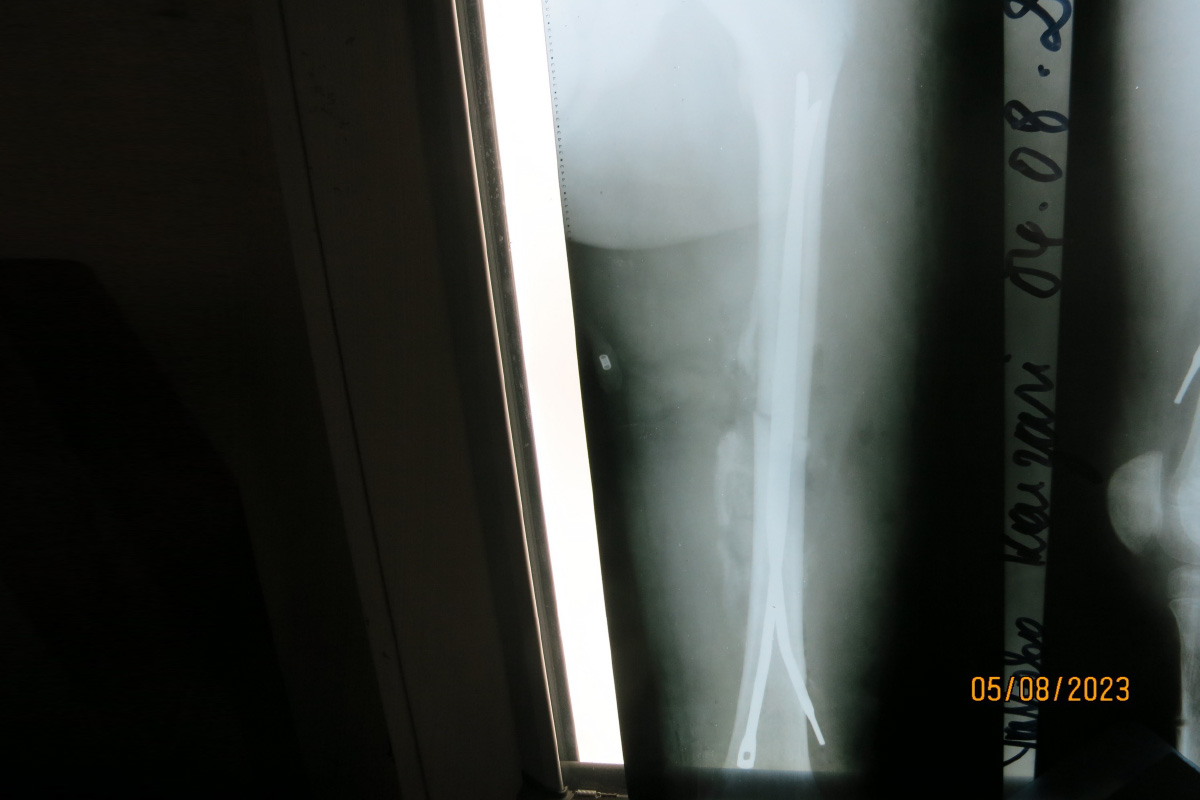

Es kommen spannende Fälle von Wachstumslenkung vor. Wie bei diesem Jungen, der zu Beginn der Behandlung fünf Jahre alt war. Der Beginn der Behandlung in so geringem Alter war notwendig, weil die Deformität so invalidisierend war, dass die Einschulung im folgenden Jahr wohl nicht möglich gewesen wäre.

Natürlich kommt auch viel Kinder-Traumatologie vor. Hier ist ein Beispiel von ECMES/ESIN eines Femurs mit Hilfe von Ender-Nägeln, die auch aus den Beständen der Tuttlinger Klinik stammen, die in Deutschland als nicht mehr als zeitgemäß gelten.

Bei Arielle brachten wir im August 2017 Klammern an der Außenseite des rechten Kniegelenkes an, um die O-Bein-Stellung zu korrigieren (Abb. 5). Nach einigen Monaten war die Achsfehlstellung ausreichend ausgeglichen. Es blieb jedoch weiterhin die Überlänge des rechten Beines bestehen.

Um dieses Längenproblem zu behandeln, wurden im August 2018 zusätzlich Klammern an der Innenseite derselben Wachstumsfuge eingesetzt (Abb. 6). Dadurch wurde das Wachstum des rechten Beines insgesamt verlangsamt, ohne es vollständig zu stoppen. Andere Wachstumsfugen blieben weiterhin aktiv, jedoch wuchs das behandelte Bein nun langsamer als das unbehandelte linke. Auf diese Weise erhielt das linke Bein die Möglichkeit, im Wachstum aufzuholen.